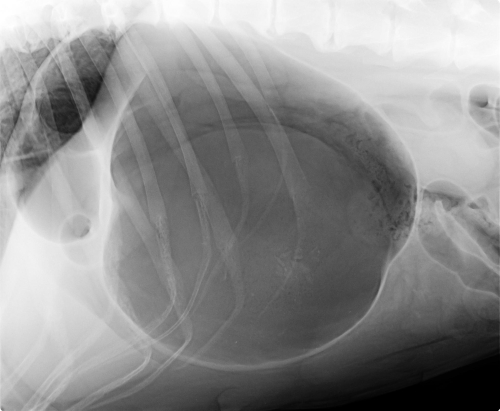

Syndrom dilatace a torze žaludku (GDV – z angl. gastric dilatation – volvulus), tedy roztažení a otočen je velmi akutní onemocnění ohrožující život, které vyžaduje okamžitou chirurgickou pomoc veterinárního lékaře.